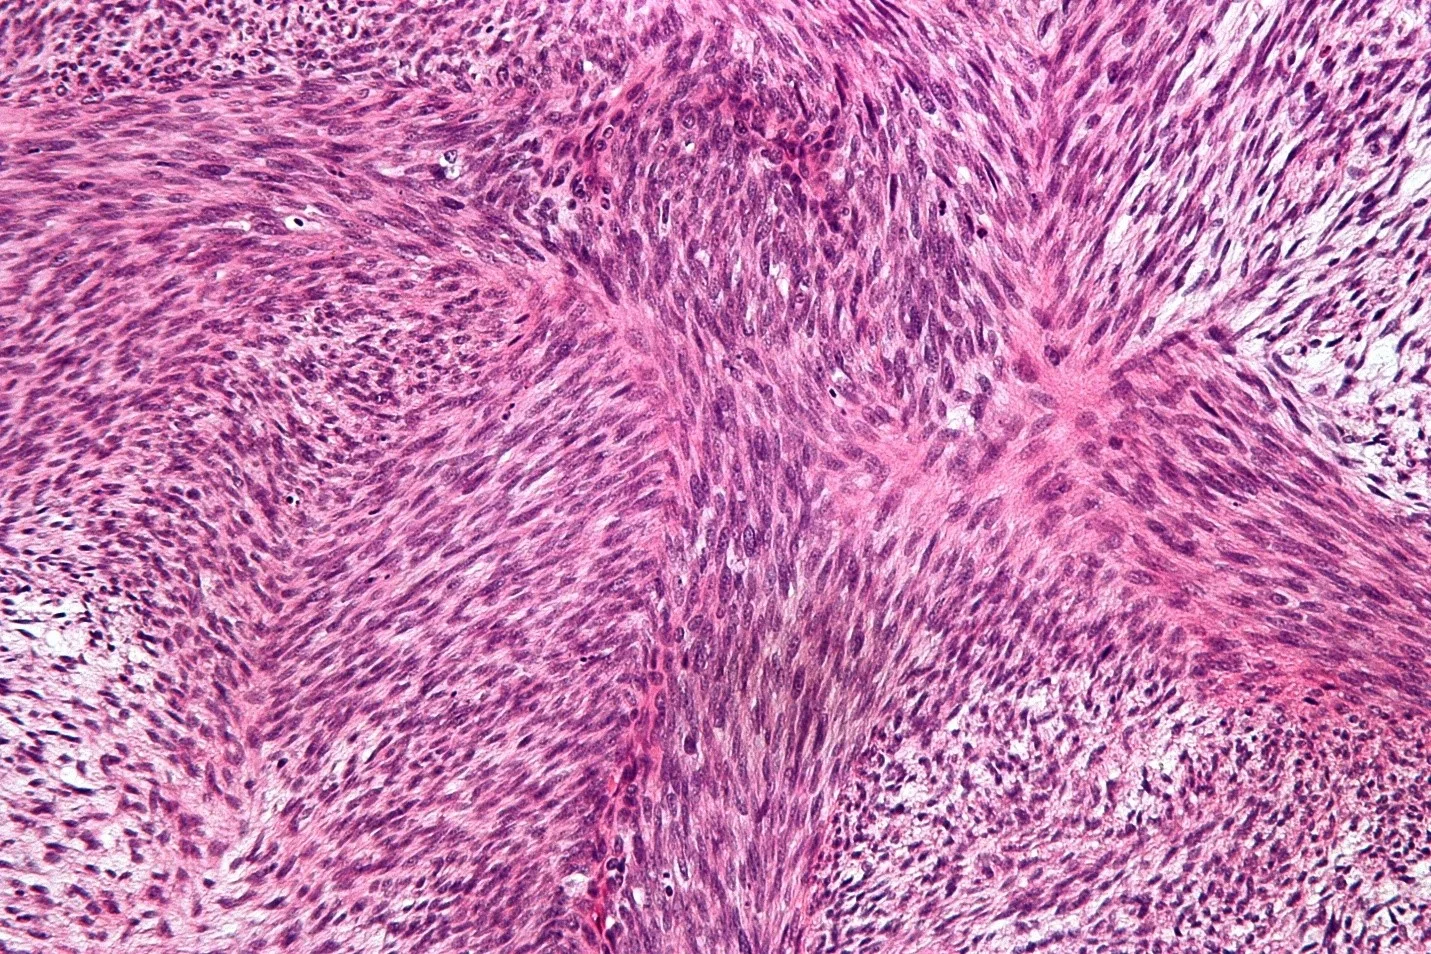

- فیبروسارکوم بزرگسالان (Adult fibrosarcoma) معمولاً بافت فیبری را در پاها، بازوها یا تنه تحت تأثیر قرار میدهد. این بیماری بیشتر در افراد بین 20 تا 60 سال شایع است اما میتواند در افراد در هر سنی و حتی در نوزادان نیز رخ دهد.

- سارکوم فیبرومیکسوئید (Fibromyxoid sarcoma) با درجه پایین سرطانی با رشد آهسته است که اغلب به صورت توده بدون درد در تنه یا بازوها و پاها (به ویژه ران) شروع میشود. در افراد جوان تا میانسال شایع تر است. گاهی اوقات تومور ایوانز (Evans’ tumor) نامیده میشود.

- فیبروماتوز (Fibromatosis) نامی است که به تومورهای بافت فیبری با ویژگیهای بین فیبروسارکوم و تومورهای خوش خیم مانند فیبروم داده میشود (به مباحث زیر مراجعه کنید). آنها به آرامی اما اغلب به طور پیوسته رشد میکنند. آنها همچنین تومورهای دسموئید (desmoid tumors) و همچنین با نام علمی تر فیبروماتوز عضلانی آپونورتیک (musculoaponeurotic fibromatosis) یا فقط فیبروماتوز تهاجمی (aggressive fibromatosis) نامیده میشوند. آنها به ندرت و یا هرگز، به نقاط دورتر بدن گسترش مییابند اما میتوانند با رشد در بافتهای مجاور مشکلاتی ایجاد کنند. آنها گاهی اوقات حتی میتوانند کشنده باشند. برخی از پزشکان آنها را نوعی فیبروسارکوم با درجه پایین میدانند اما برخی دیگر معتقدند که آنها یک نوع منحصر به فرد تومور بافت فیبری هستند. برخی هورمونها مانند استروژن باعث رشد برخی از تومورهای دسموئید میشوند. داروهای ضد استروژن گاهی اوقات برای درمان دسموئید مفید هستند که نمیتوان آنها را بهطور کامل با جراحی از بین برد.